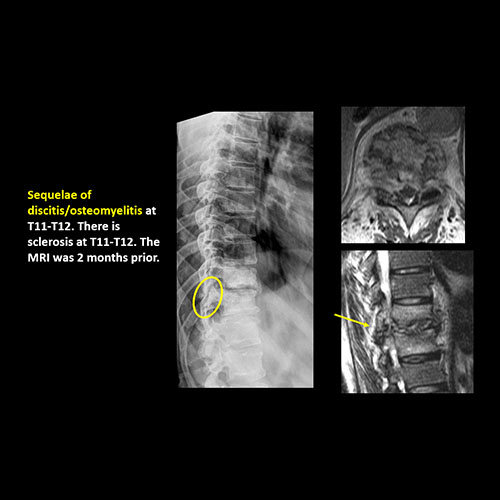

There is evidence of a lytic, sclerotic, or blastic lesion, or disruption of the trabecular pattern of a vertebral body, end plate, or rib. |

Yes | NA |

There is disc space narrowing with or without erosive or sclerotic changes of the end plates or subchondral bone other than from degenerative change. |

There is an oblique fracture with avulsion through the anterior inferior T9 vertebral body. The posterior elements are intact. There is excessive calcification of the anterior longitudinal ligament and there are continuous osteophytes in a pattern consistent with DISH (Diffuse Idiopathic Skeletal Hyperostosis).